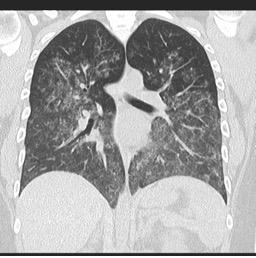

Difuzno alveolarno krvarenje zbog vaskulitisa

Izvor: radiopaedia.org

o HRCT: Difuzne ground-glass opacitete i alveolarne konsolidacije.

o CT visoke rezolucije (HRCT): Prikazuje difuzne ground-glass opacitete i talog hemosiderina

o HRCT: Pokazuje intersticijsku bolest pluća i ground-glass opacitete